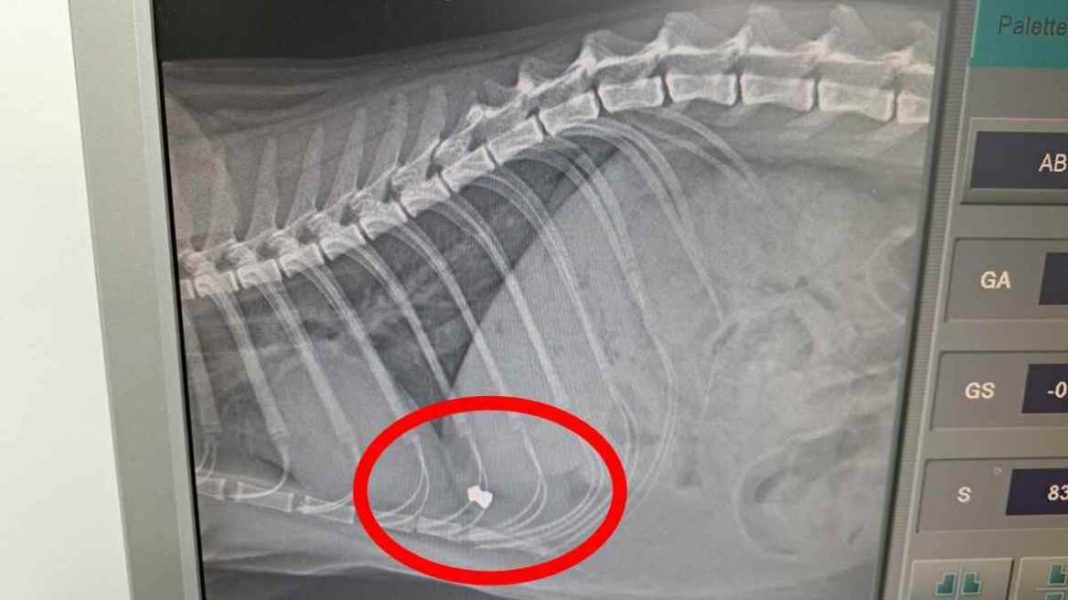

Αρχικά, η οικογένειά του πίστεψε ότι είχε παγιδευτεί κάπου, καθώς ήταν εξαντλημένος και καλυμμένος με κόλλες. Ωστόσο, η αλήθεια αποδείχθηκε πολύ πιο εφιαλτική. Η ακτινογραφία αποκάλυψε ότι το ζώο είχε πυροβοληθεί με αεροβόλο όπλο.

Σύμφωνα με την ανάλυση των τραυμάτων του, το αεροβόλο είτε είχε εξαιρετικά υψηλή ισχύ είτε χρησιμοποιήθηκε από πολύ κοντινή απόσταση, καθώς η μεταλλική σφαίρα διαπέρασε ολόκληρο το σώμα του και σταμάτησε στην αντίθετη πλευρά. Ο γάτος σώθηκε από καθαρή τύχη, αφού η σφαίρα δεν έπληξε κάποιο ζωτικό όργανο.